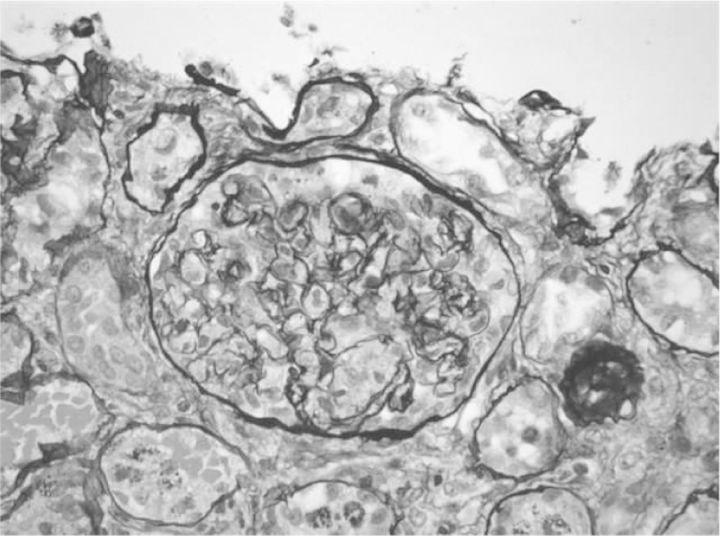

单剂量奎宁引发的肾局限性血栓性微血管病和急性间质性肾炎。

Renal-limited thrombotic microangiopathy and acute interstitial nephritis with a single dose of quinine.

Quinine has been reported to cause acute kidney injury by various mechanisms. The response to quinine can result in a spectrum of problems ranging from isolated thrombocytopenia to thrombotic microangiopathy (TMA) to disseminated intravascular coagulation. Quinine has also been reported to cause acute interstitial nephritis (AIN). We report an unusual presentation where both of these entities of renal-limited TMA and AIN were precipitated by a single dose of quinine.

摘要

据报道,奎宁可通过多种机制导致急性肾损伤。对奎宁的反应可能会引发一系列问题,从孤立性血小板减少到血栓性微血管病(TMA),再到弥散性血管内凝血。也有报道称奎宁可导致急性间质性肾炎(AIN)。我们报告了一例罕见病例,单次服用奎宁引发了局限于肾脏的TMA和AIN这两种情况。